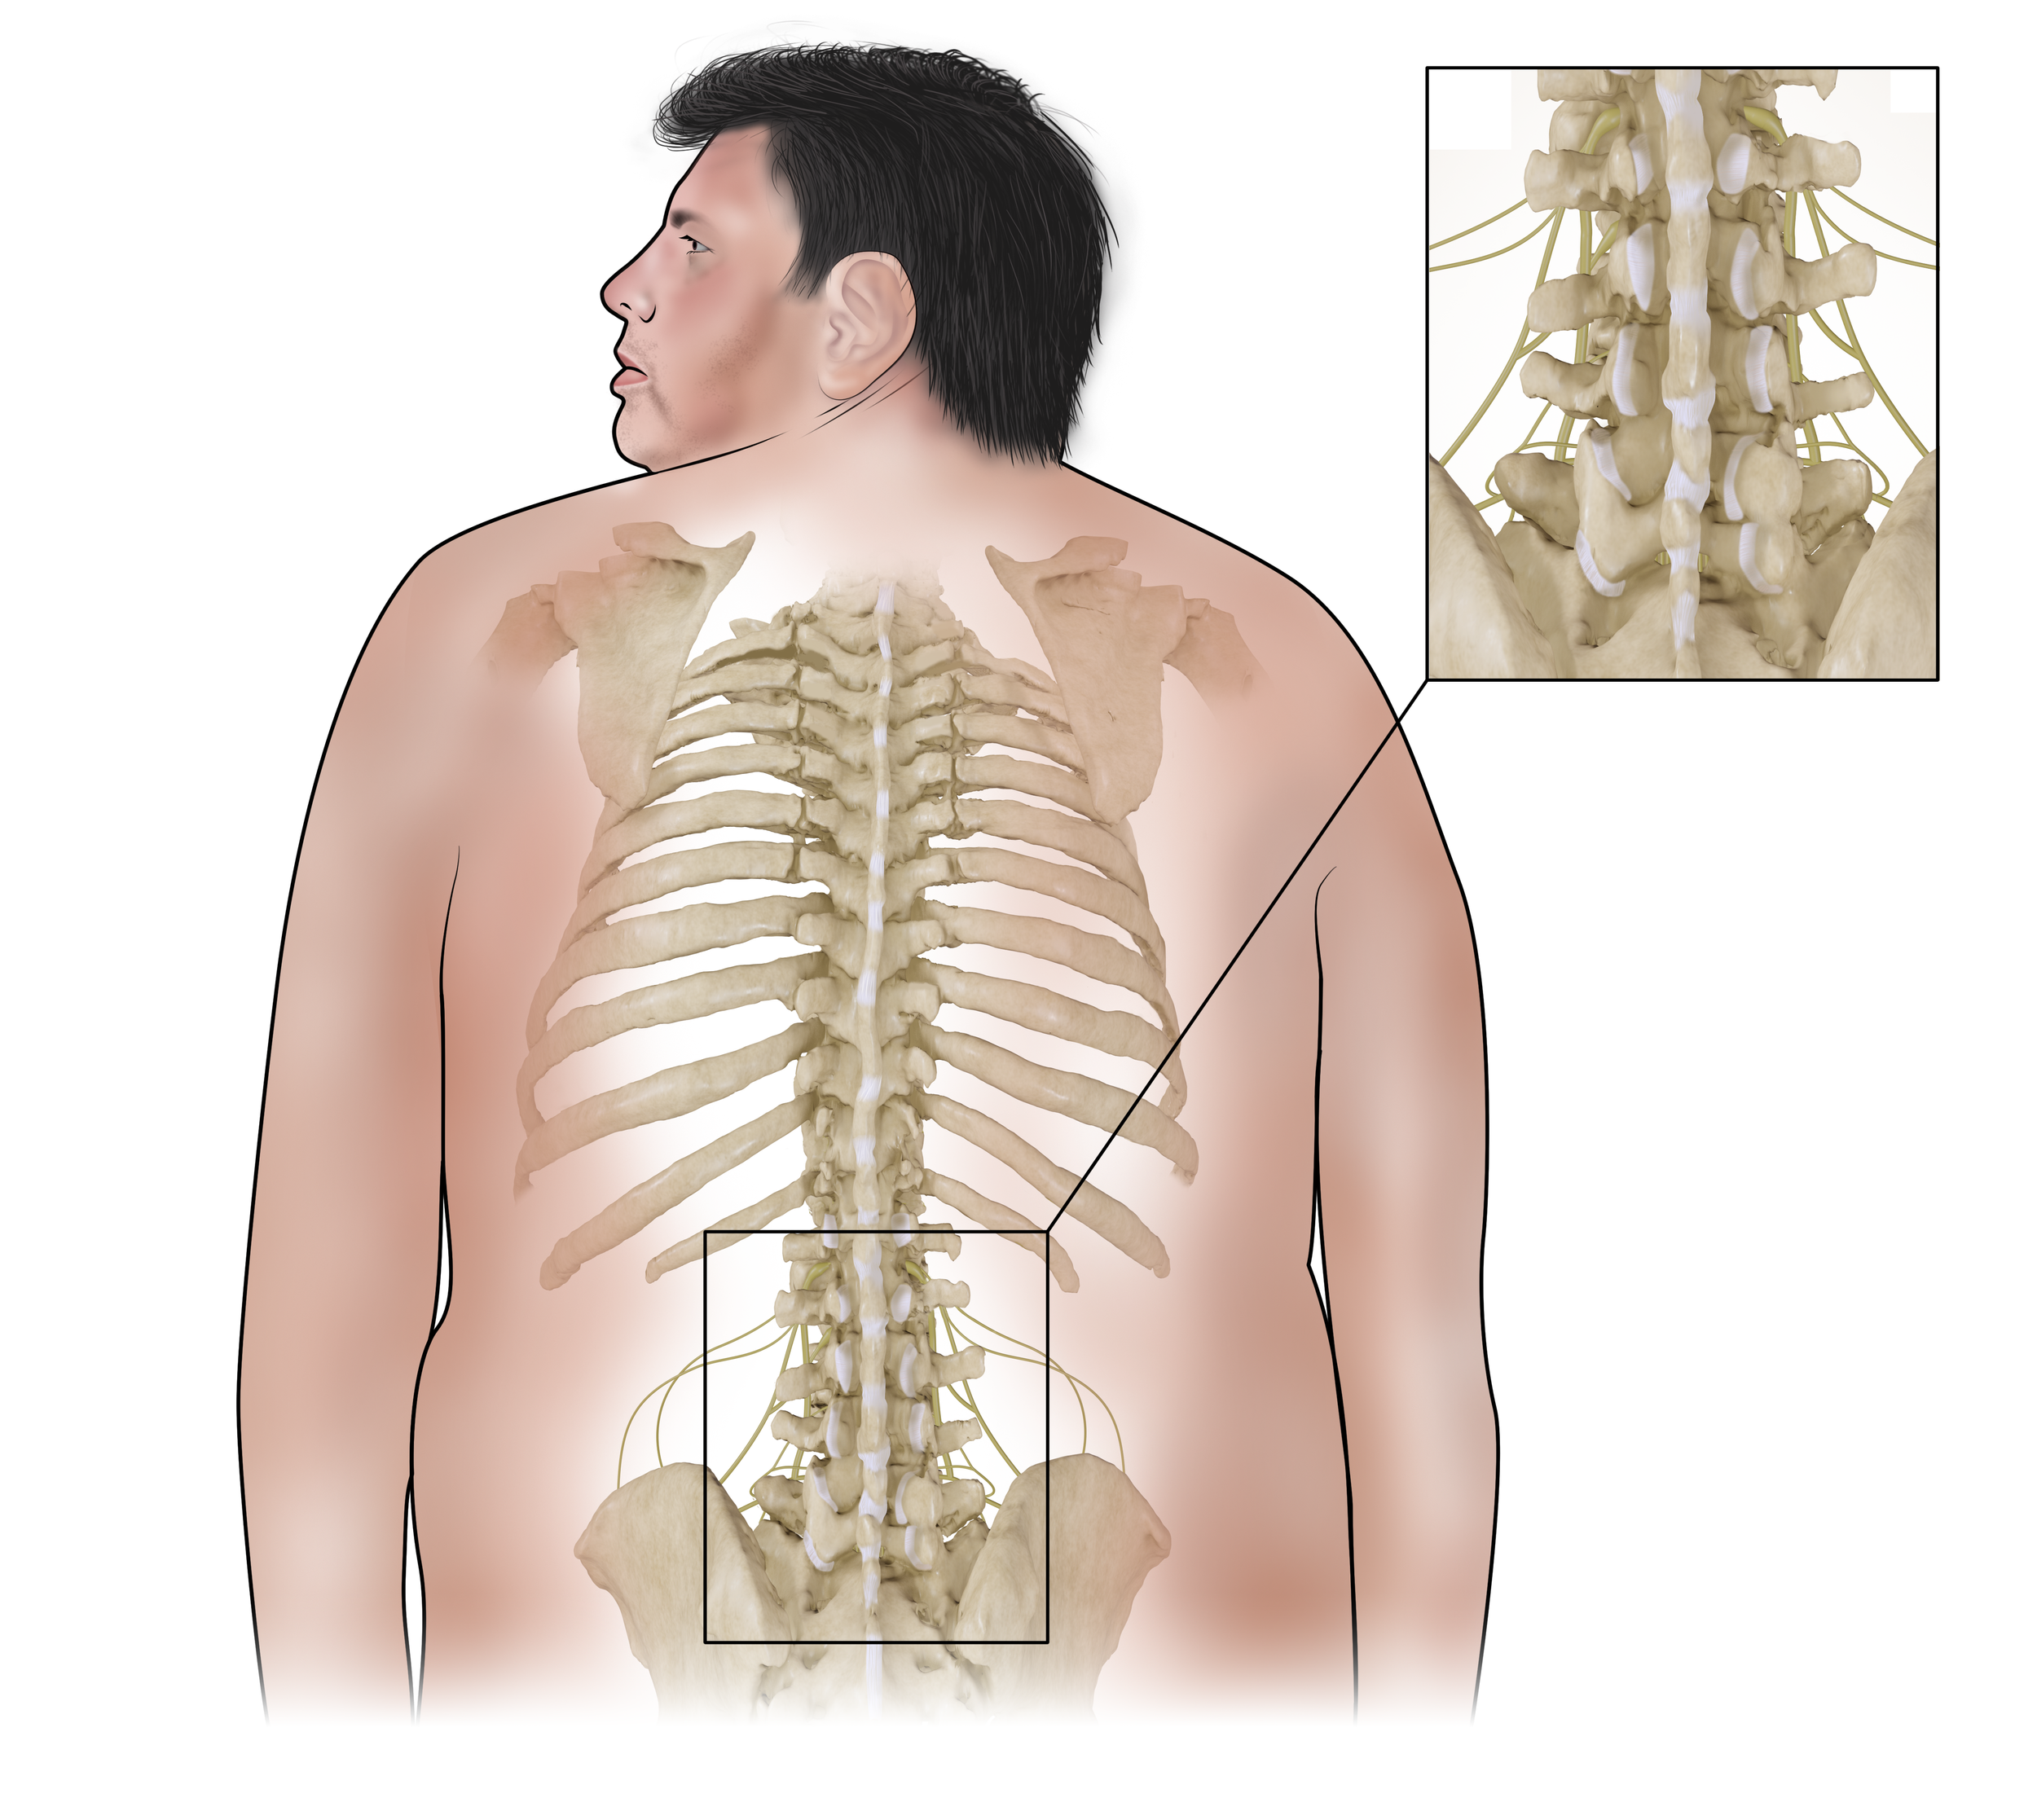

Uninjured Lumbar Region

Created from CT using 3D modeling and Photoshop.